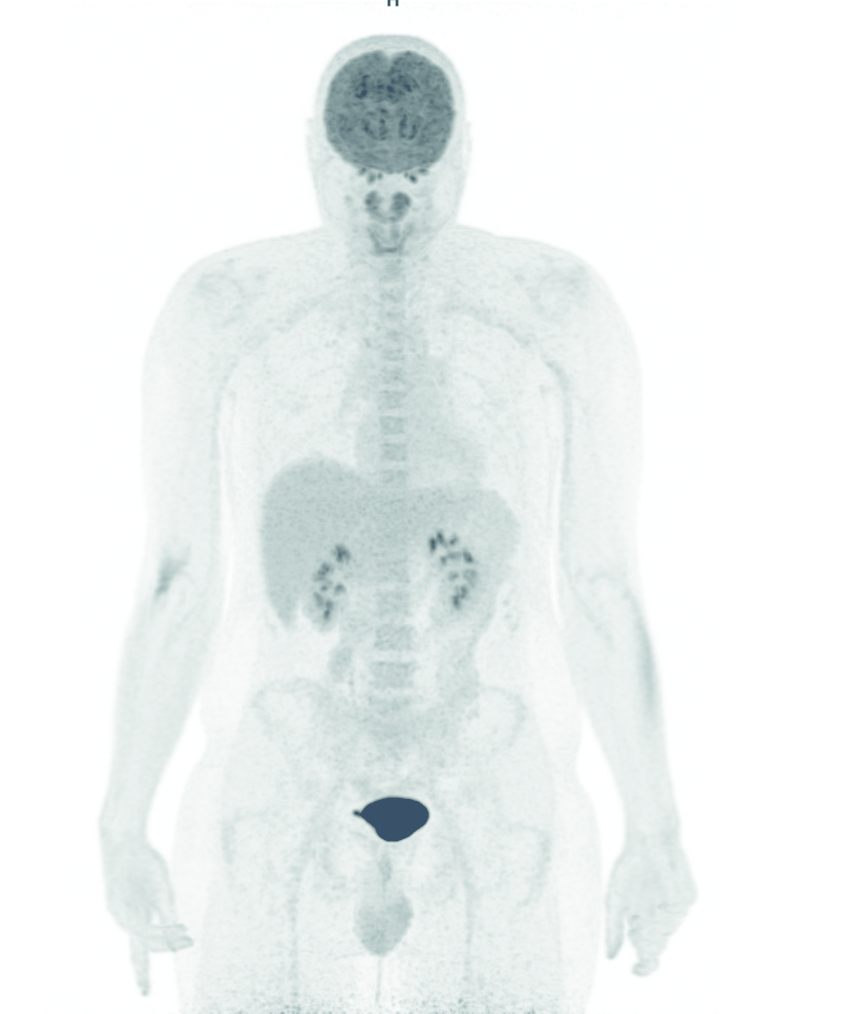

Fig. 132.5 Image MIP d’une tomographie par émission de positons au 18F-fluorodésoxyglucose (TEP-FDG).

Distribution physiologique « corps entier » du FDG.